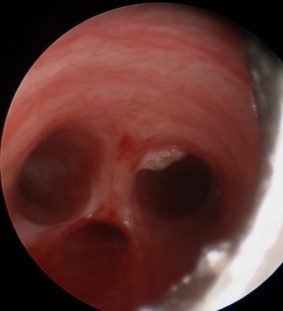

Fig. 1